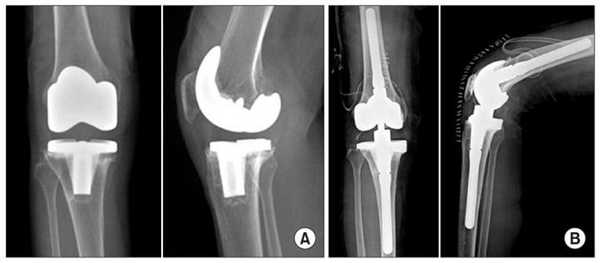

Сравнение двух типов операций.

Две техники операции у одного пациента.